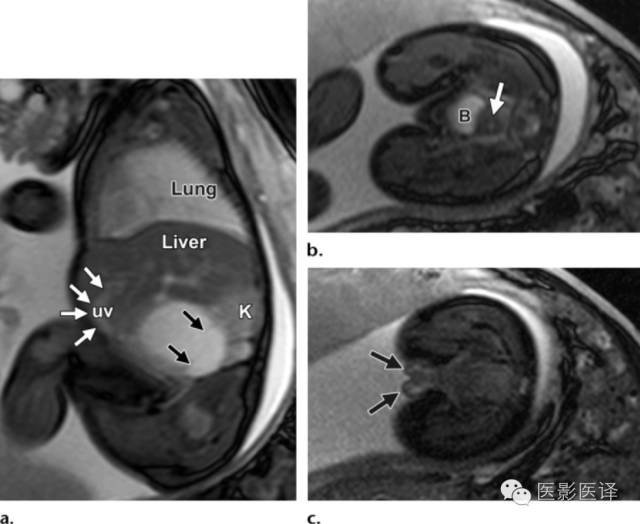

图3:单纯性卵巢囊肿。(a)矢状位胎儿超声图像显示一个边界清楚薄壁腹内囊肿(箭头),其内可见一个子囊(箭)。囊肿位于膀胱(B)上方腹中线区。Uv=脐静脉。(b)同一病人轴位超声多普勒图像显示在薄壁卵巢囊肿中有两个子囊(箭头)